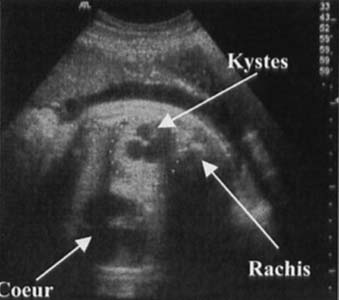

Masse hétérogène (forme macrokystique)